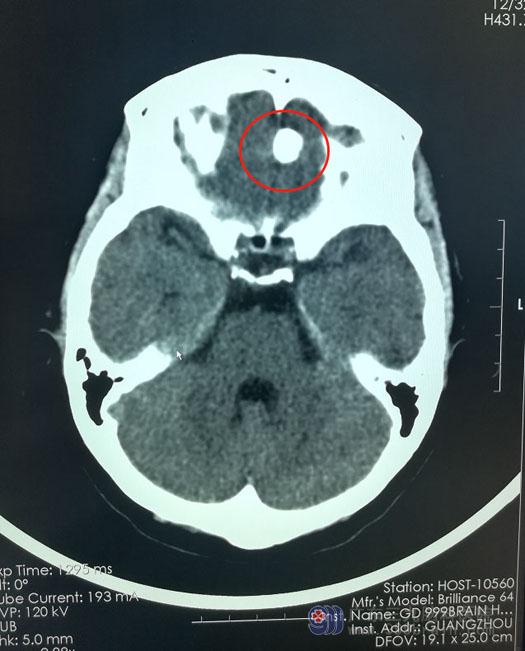

2个月前,60岁的陈阿姨出现间断性的头晕,休息后可缓解。近几次头晕症状加重并伴有轻度的头痛。在当地医院检查,头颅CT提示:左侧前颅窝占位病变,考虑脑膜瘤。

入住广东三九脑科医院神经外五科后,主管医生卢建侃为陈阿姨安排了相关的检查,颅脑MRI提示:前颅窝底左侧额部镰旁占位性病变,考虑钙化为主的脑膜瘤可能性大。

最终,陈阿姨决定听从医生的建议,接受手术治疗。由鲁明主任主刀在全麻下为陈阿姨实施经左侧眉弓锁孔入路行前颅窝底左侧额部镰旁脑膜瘤切除术,手术过程顺利,病变被完全切除。